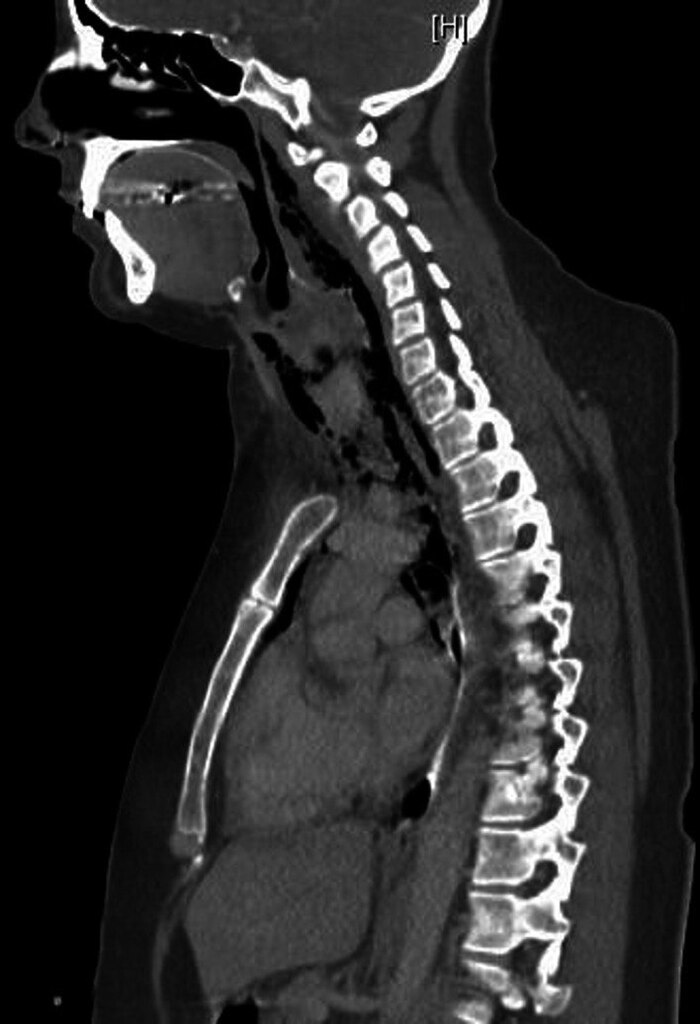

Компьютерная томография продемонстрировала обширную эмфизему мягких тканей шеи и грудной клетки от основания черепа до средостения Фото 2.

Figure 2. Компьютерная томография в сагиттальном разрезе демонстрирует наличие внепросветного воздуха, распространяющегося от уровня носоглотки до средостения.